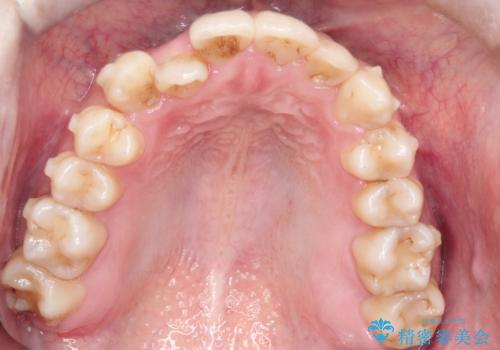

- 八重歯を治したいとのことで来院されました。

右上の犬歯が外側に飛び出して、二番目の歯が内側に入っている状態でした。

上の奥歯を後方に移動させてスペースを確保して、前歯のガタガタを改善する計画としました。